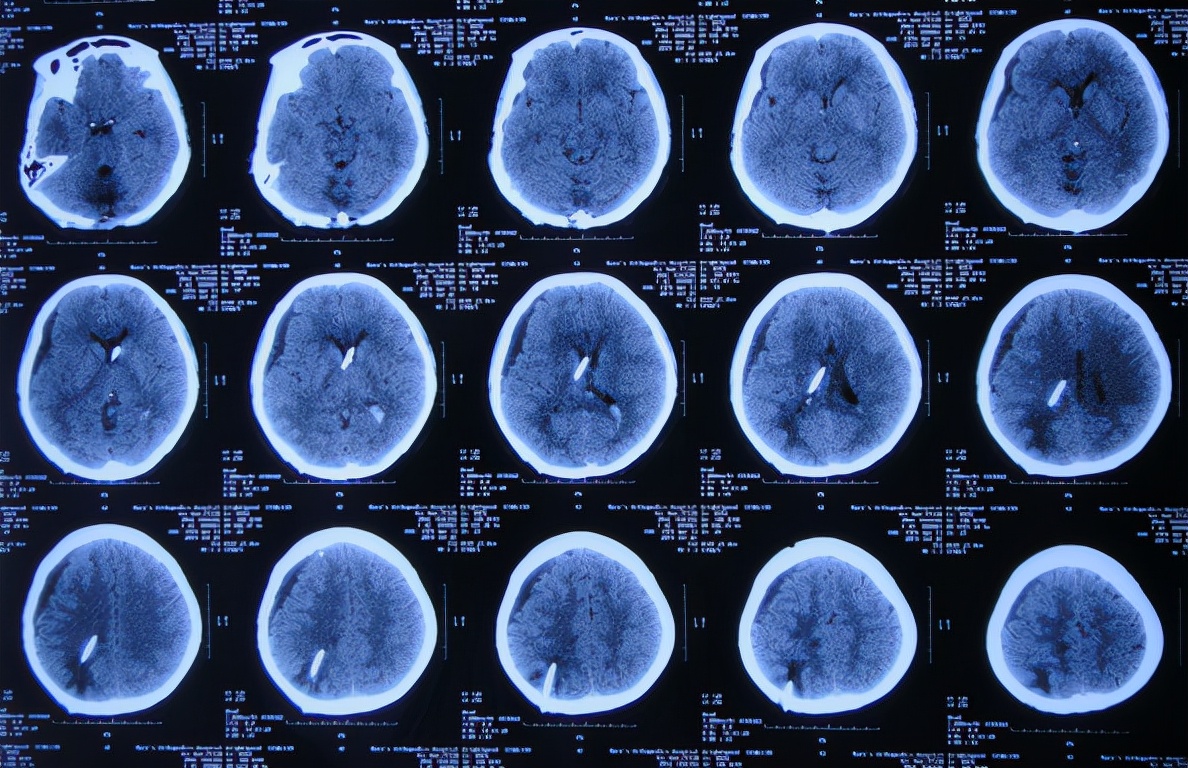

入院治疗17天即2019年7月8日,入院时不能眨眼已变基本正常,头部疼痛较入院时有减轻( 图-22 );查头颅CT示虽有少量硬膜下积液,但脑室基本正常( 图-23 )。

图-22: 2019年7月8日

图-23: 2019年7月8日头颅CT

入院治疗53天即2019年8月13日,进行了脑室腹腔分流术( 图-24 )。

图-24: 2019年8月13日头颅CT

2019年8月23日(李小勇脑脊液科治疗63天)出院,出院时:精神变好,眨眼变正常,入院时睡觉时有尿*禁失**完全消失;颈部,肩部疼痛显著减轻,但走路稍不稳( 图-25 );出院前头颅CT示未见异常( 图-26 )。

图-25: 2019年8月23日

图-26: 出院前头颅CT